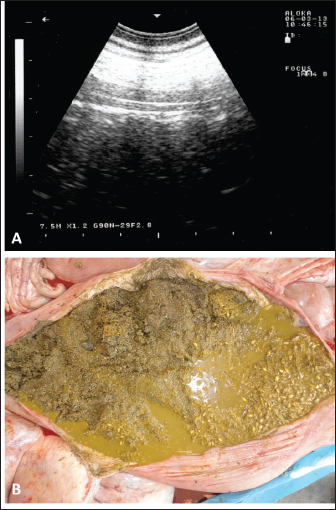

Sonographic and postmortem findings are summarized in Table 2. In cases of camels presented with a history of pica and with decreased or total absence of feces, the obstructing foreign body was imaged in 10 of the 25 camels (40%) occluding completely or partially the intestines that may be confirmed at abdominal surgery (Figs. 2, 3, and 6). Foreign bodies within the rumen could not be visualized with ultrasound owing to the gas content. In cases where the rumen is impacted by sand, small pin-points revealing acoustic enhancement were imaged in 5 (20%) of the camels. An example of these cases is shown in Figure 7. Foreign bodies were removed from the rumen or intestines at exploratory rumenotomy and laparotomy, which included plastics, cloths, sand, mud, robes, wool balls, glasses, or even metallic objects that were blunt or sharp (Figs. 8 and 9).

Fig. 7. Ultrasonographic and postmortem findings in an adult female camel with a history of pica and decreased fecal output and abdominal distension. Image (A) was taken using a 3.5 MHz sector transducer and shows sonography of the rumen from the left lower abdomen where several pin-points acoustic shadowing were imaged. Image (B) shows large amounts of sand within the rumen detected at postmortem examination.

During the past 13 years, our research group has focused on the effectiveness of diagnostic imaging techniques in dromedary camels either in the healthy or diseased conditions (El-Tookhy and Tharwat, 2012; Ali et al., 2018; Al-Sobayil et al., 2018; Tharwat et al., 2012a,b,c,d; Tharwat, 2013a; Tharwat et al., 2013; Tharwat and Al-Sobayil, 2016a; Tharwat et al., 2018a; Tharwat, 2019; Tharwat, 2020a,b,c; Tharwat, 2021a,b; Tharwat and Al-Hawas, 2021; Tharwat and El-Tookhy, 2021; Tharwat et al., 2021; Tharwat and Al-Hawas, 2023; Tharwat et al., 2023; Tharwat,$ 2024; Tharwat and Al-Hawas, 2024). In these studies, the occluding foreign body was imaged obstructing the intestines either partially or completely. Because of the gaseous contents, the foreign bodies could not be localized within the rumen. However, in camels with rumen sand impaction, shining pin-points with acoustic enhancement are clearly visualized.